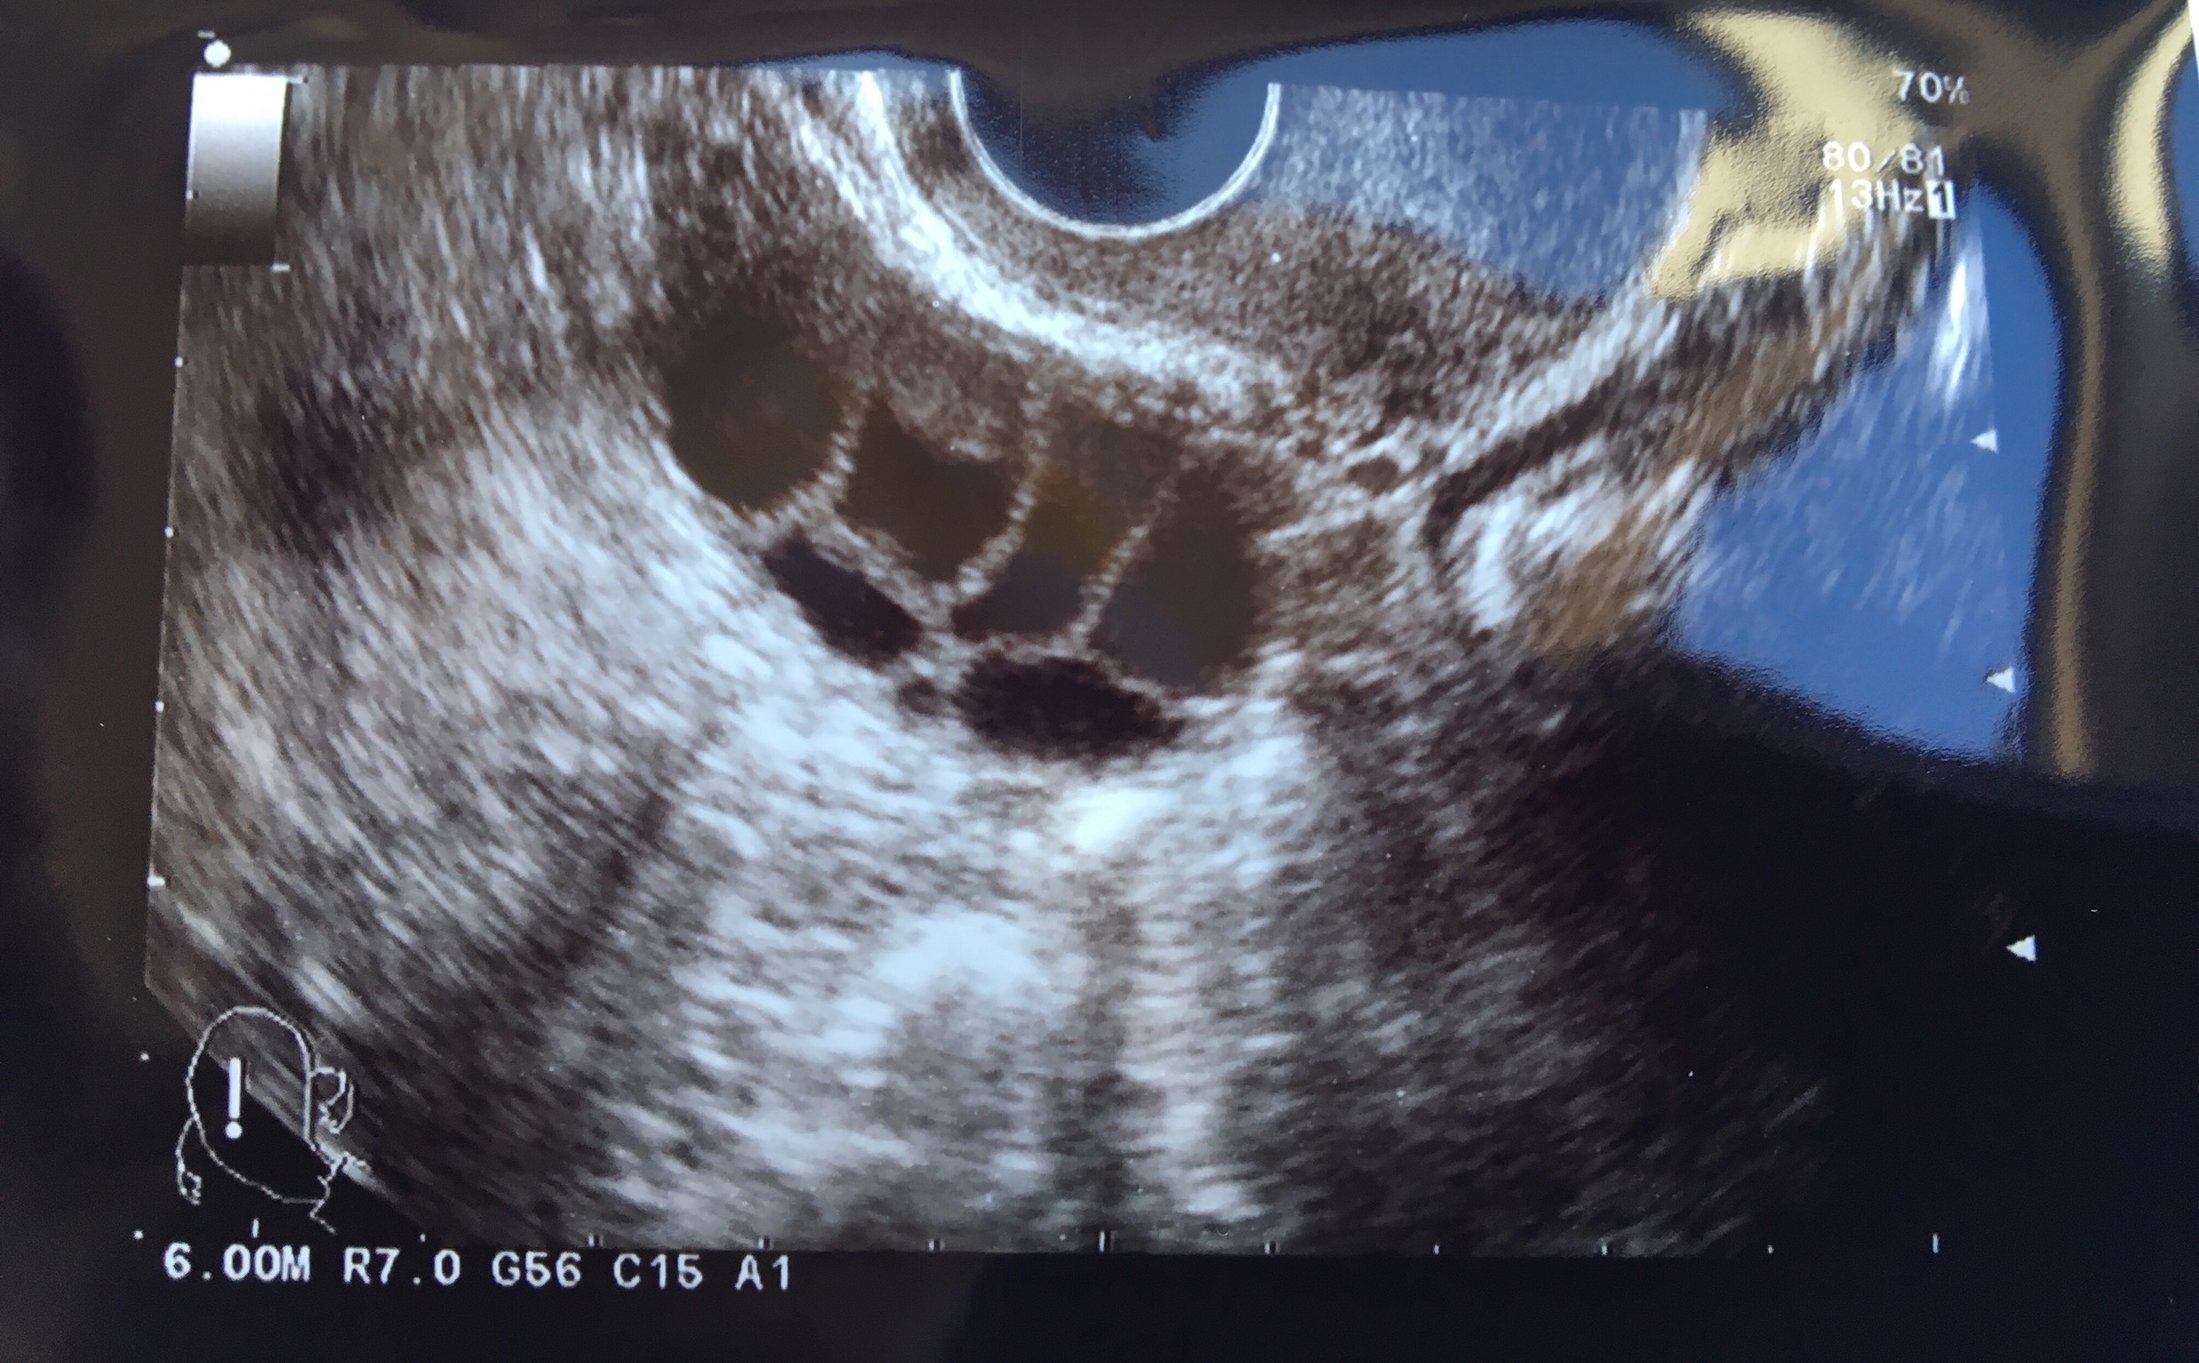

What are you doing this cycle? (Testing? Treatment?) I have my ER this week! I have a checkup later today to see all my follies. I absolutely love these appointments and find it fascinating to see all the follies on the u/s. My IVF calendar said the ER might be on Wednesday, but during Saturday's appt, the doc said that the ER might not be until Thursday or Friday. We'll see what he says later today.

She said it’s looking like I have 15 follies on the right side and 14 on the left. (OMG) They are measuring at about 14-15 right now, the biggest one stomping in at 17. They want me to come back tomorrow to see if it’s time to trigger!